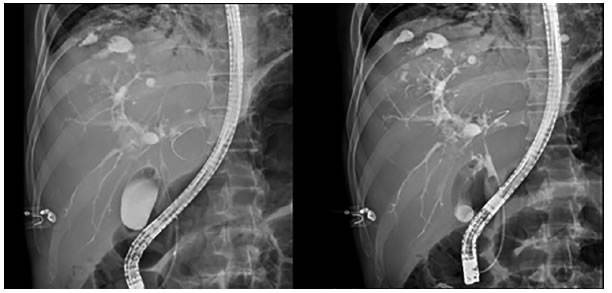

En la colangiopancreatografía endoscópica retrógrada (CPRE) se encontraron múltiples irregularidades y dilataciones saculares por colangitis, y una colección en los segmentos superiores del hígado e importante disminución del calibre del conducto hepático común (figura 2).